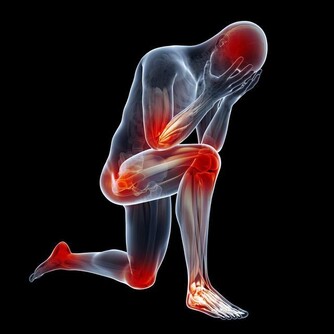

這是一種影響所有年齡段人群的長期病症。最常見的類型是骨關節炎,由關節內光滑的軟骨逐漸磨損引起的。其症狀包括關節疼痛、壓痛、僵硬,並且在受影響的關節上皮膚會出現紅腫。

跟其他炎症不同的是,我們很難做到完全不刺激有炎症的關節,除非你打上石膏保證那裡的關節不活動,但可操作性太差。這也就意味著,你會經常刺激到有炎症的關節,那種滋味你可以想像到,不會太好受。